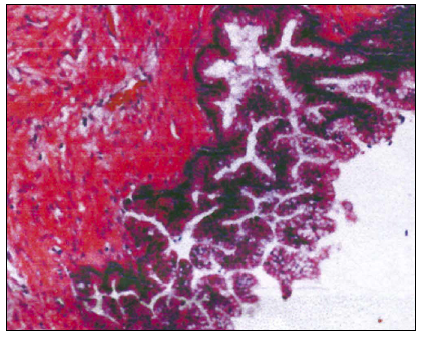

Microscopically, it presented proliferation of glandular structures of multiple shapes and forms with areas of flattening of the epithelium and atrophic aspect. No malignant activity was reported and the base of the appendix was free of neoplasia (Figure 3).